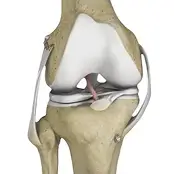

Knee Orthopedic Surgery